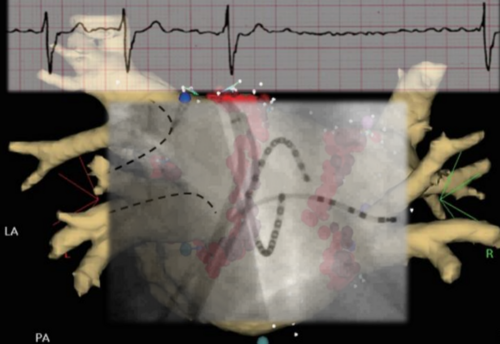

Fibrillation auriculaire

"Fibrillation auriculaire : connaissances actuelles et nouveautés 2024"

C'est avec un grand plaisir que je vous invite à participer à une formation exceptionnelle sur le sujet de la fibrillation auriculaire. Exceptionnelle, car nous accueillons Pr Christian Sticherling et son équipe de la rythmologie de l’Hôpital Universitaire de Bâle. Ils vont nous présenter un tour d'horizon de cette pathologie avec toutes les nouvelles techniques invasives utilisées. Cet événement est aussi remarquable par l’implication des cardiologues jurassiens qui présenteront pour chaque sujet une situation clinique mettant en pratique les interventions universitaires. Enfin, la population jurassienne profitera également de la venue des spécialistes bâlois, puisqu’ils donneront une conférence publique au terme de la formation des médecins à partir de 18h30.

• 16h05 – 17h00 Thérapie invasive

Conférence State of the art : Pr Dr méd. Christian Sticherling